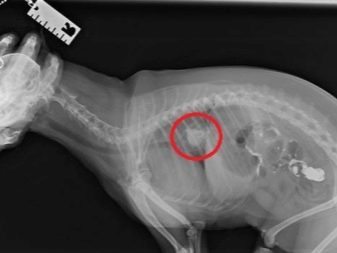

• It happens that small fragments of bones are collected in the stomach into a dense conglomerate, which cannot be expelled from the dog’s body by natural means. Cleansing enema, oil rectal suppositories, and in more complex cases, surgical surgery will help alleviate the condition.